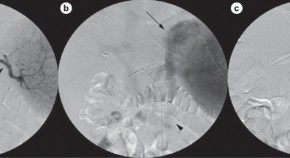

• This article considers the case of a 49-year-old woman with a history of hepatitis C and peptic ulcer disease who presented with massive hematemesis. She was diagnosed with gastric variceal hemorrhage and splenic vein thrombosis. The patient underwent splenic artery embolization and balloon-occluded retrograde transvenous obliteration of gastric varices. By 30 months post-treatment no evidence of gastric varices or splenic vein thrombosis remained.

• Vanessa Tieu

• George Behrens

• Joseph Ahn